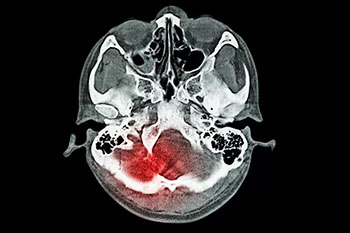

蛛网膜下腔出血是出血性脑血管病的一种,这种疾病和普通的脑出血是不一样的,普通的脑出血一般都是指脑实质内出血,而蛛网膜下腔出血,它是由于脑子里面出血,年轻患者蛛网膜下腔出血大多数都是因为颅内动脉瘤或者脑血管畸形,而老年人患这种疾病一般为动脉瘤脑动脉硬化,这种疾病的病情变化非常快,病情很危重,所以一旦出现头痛的话,可能就会对患者出现昏迷等各种的不良反应影响,严重的话,可能会危及生命。

蛛网膜下腔出血是一种症状表现,由于多种原因引起的脑血管突然破裂,是血液进入颅内或椎管内的蛛网膜下腔所引起的综合征。临床上将蛛网膜下腔出血分为自发性和外伤性两类。

蛛网膜下腔出血的治疗是一项综合治疗,目的是为了防止再出血、血管痉挛及脑积水等并发症,降低死亡率和致残率。在确诊之后,应尽早进行脑血管造影或CT血管成像检查,一旦正式为颅内动脉瘤破裂,尽快准备实施开颅夹闭手术或血管内介入栓塞治疗。